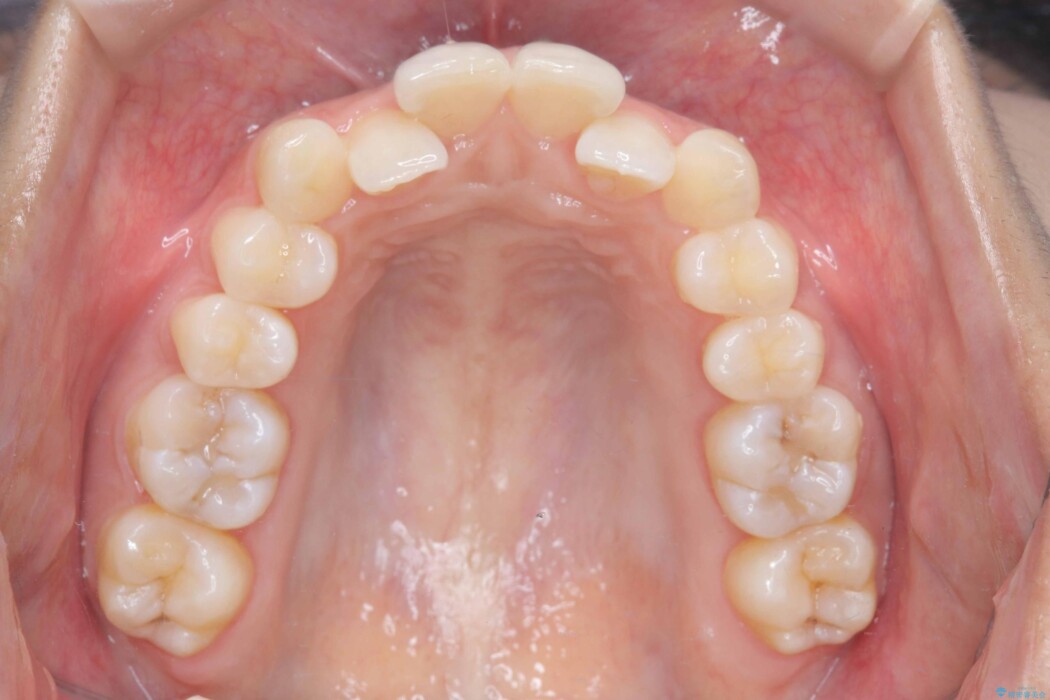

歯のガタつきが気になるとご来院された患者様です。

矯正検査の結果、非抜歯にてワイヤー矯正を行うこととしました。

ガタつきのほかに反対咬合も認められたため、見た目だけでなく嚙み合わせも同時に改善していきます。